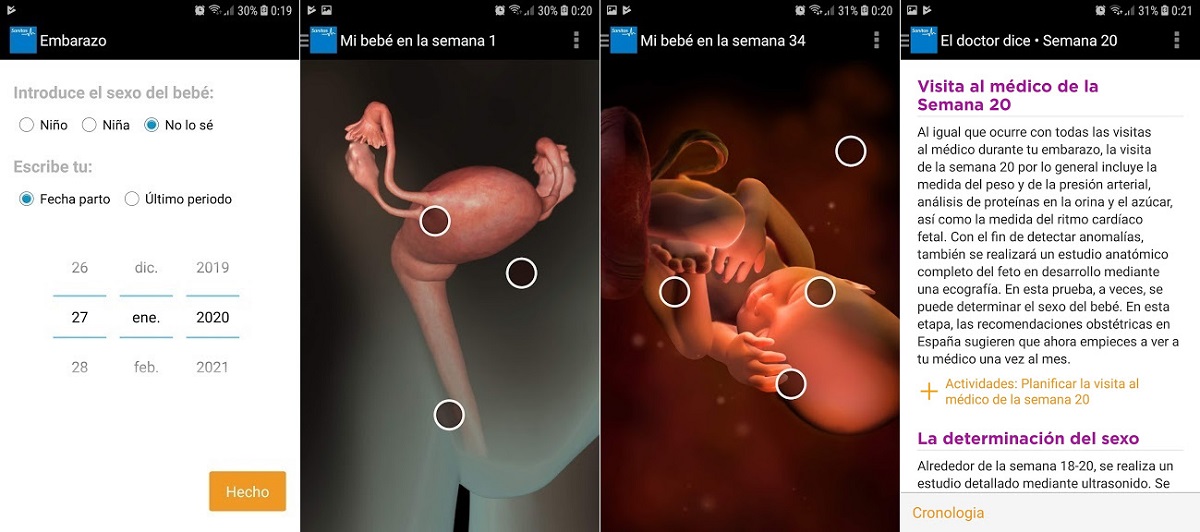

3. Sanitas Embarazo

Veamos ahora cómo funciona la aplicación de Sanitas para hacer el seguimiento del embarazo. Es un poco más sofisticada de las demás, porque te permite ver al bebé en tres dimensiones, prácticamente como si lo hicieras en una ecografía en 3D. Cada una de las imágenes contiene algunos puntos de interés, sobre los que podrás pulsar para ampliar la información.

También tienes una sección especial con consejos del doctor y un organizador, que te vendrá fenomenal para anotar las visitas médicas, las actividades a realizar y todo lo que necesitas tanto para ti como para el bebé en el momento de la verdad.